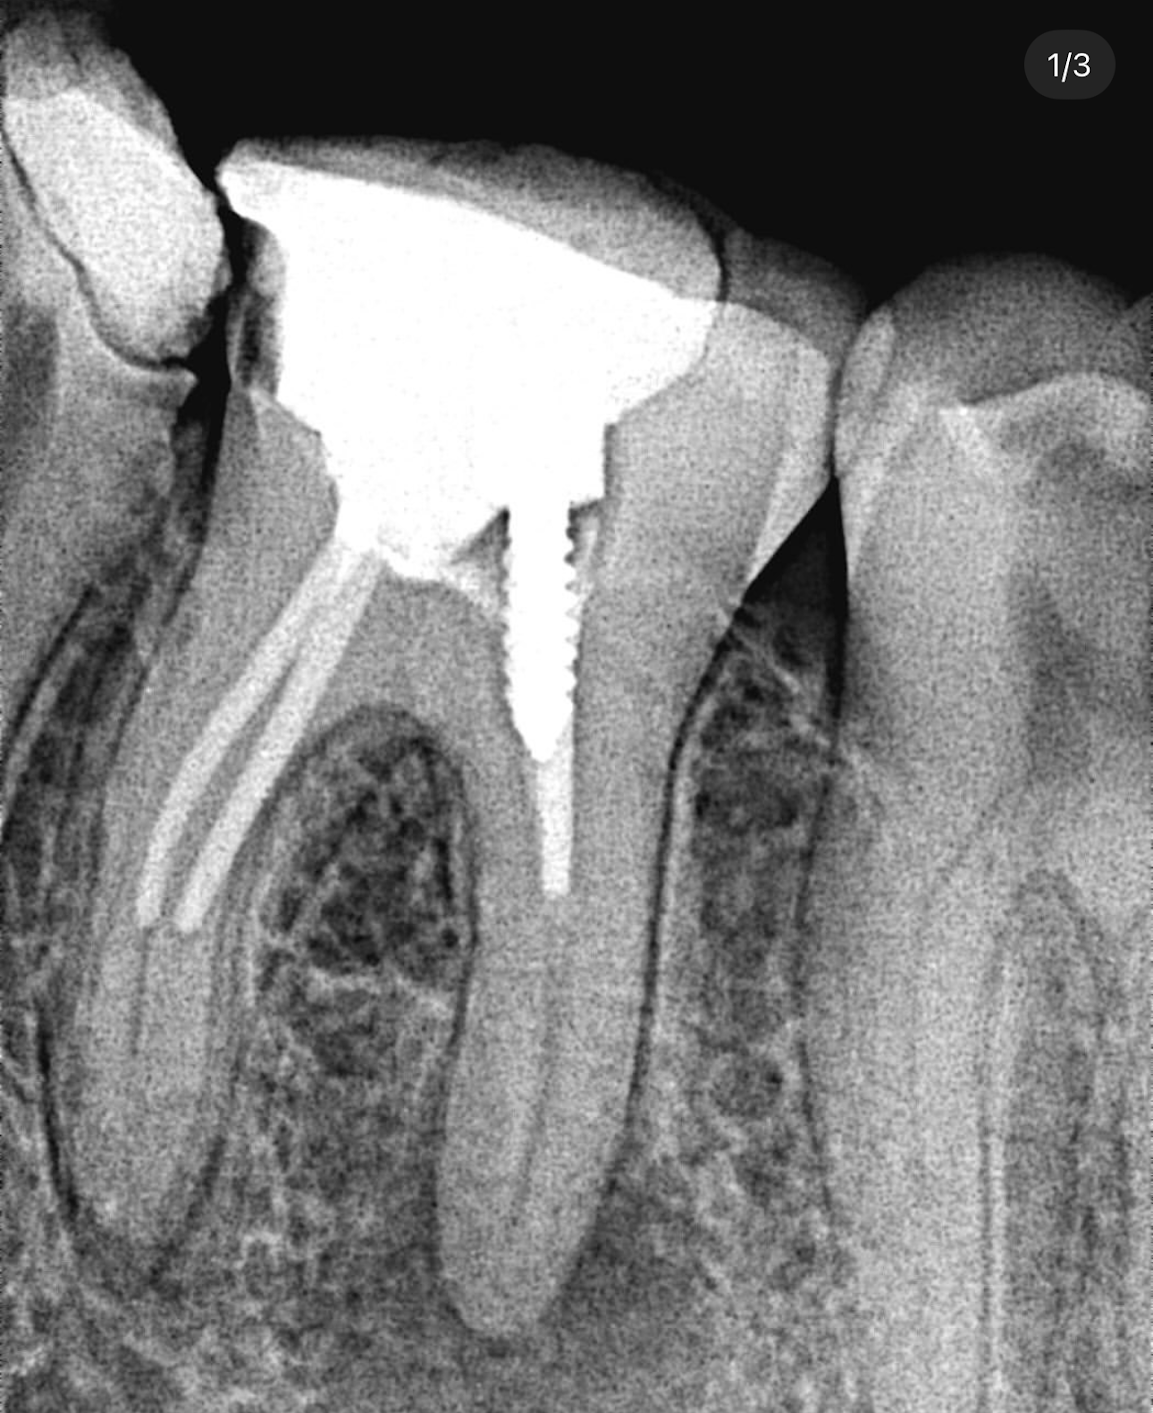

4. What option can describe the post placement in the X ray bellow for the tooth # 3.6?